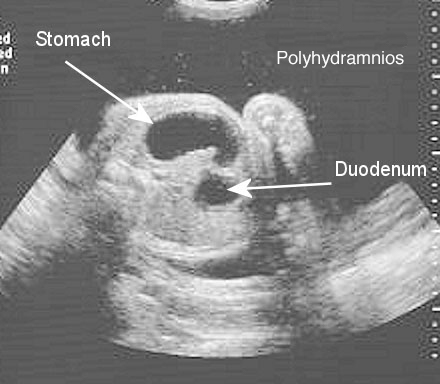

Double bubble sign on fetal ultrasound

Presence of a gastric bubble is important, but there should not be two discrete bubbles